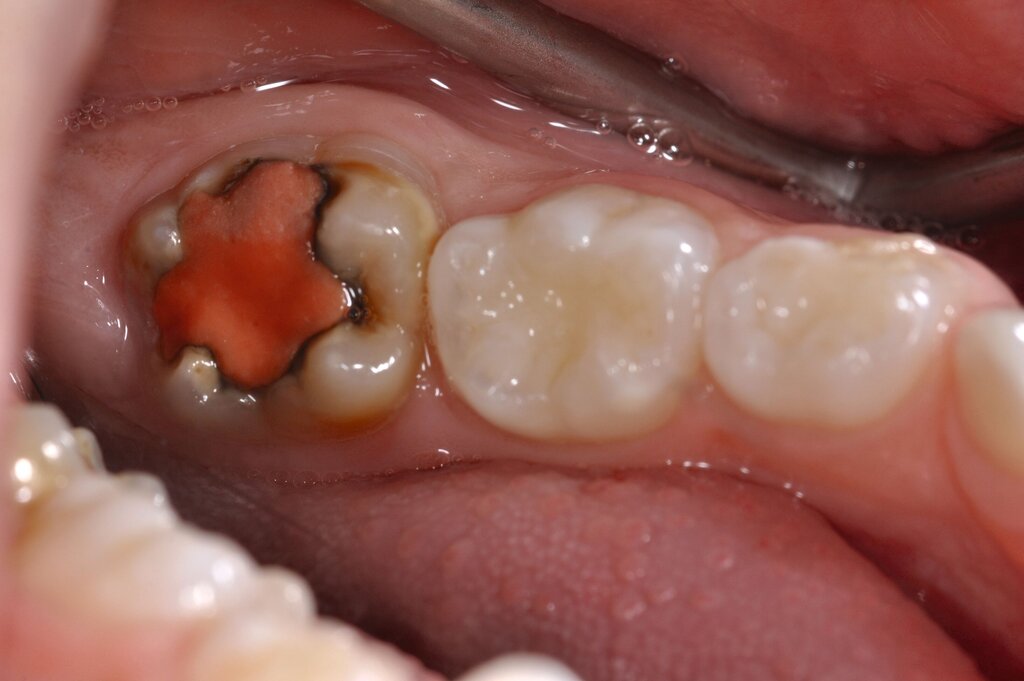

Der Vorteil der Methode ist, dass die betroffenen Zähne auch ohne Lokalanästhesie und Präparation versorgt werden können. Die temporäre Versorgung ermöglicht es, die Patienten an die zahnärztliche Behandlung zu gewöhnen. Häufig führt diese temporäre Versorgung auch zu einer Reduktion der Hypersensitivität der MIH-Zähne. Nachteil der GIZ-Versorgung ist das Risiko einer Füllungsfraktur oder eines vollständigen Verlusts der Füllung (Abbildung 4). Aktuelle Erhebungen bestätigen eine Erfolgsrate von über 80 Prozent nach einem bis zwei Jahren [Durmus et al., 2021; Mahfouz et al., 2025].

Der Behandlungsfall (Abbildung 4d) veranschaulicht die Schwächen des Verfahrens. Wird das Angebot der regelmäßigen Kontrollen nicht wahrgenommen, so droht bei Verlust der Füllung die Kariesprogression. In dem vorliegenden Fall konnte jedoch eine endodontische Maßnahme vermieden und durch die selektive Kariesentfernung die Zahnhartsubstanz weitestgehend erhalten werden.